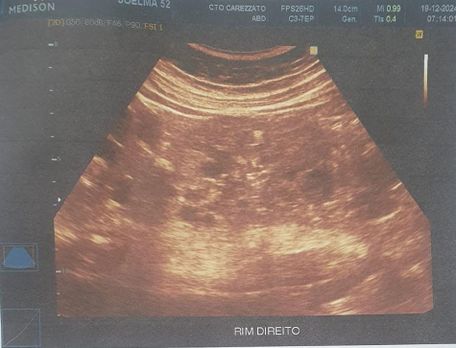

Foi realizado exame de imagem (21/10/2024), ultrassonografia abdominal com os seguintes achados (figura 1.1, 1.2, 2 e 3) Exames laboratoriais (21/10/2024): Acido úrico 2 mg/dl, Bilirrubina total 0,37 mg/dl, Bilirrubina direta 0,18 mg/dl, Bilirrubina indireta 0,19 mg/dl, TGP 21 u/l, TGO 16 U/L, Uréia 34 mg/dl, Creatinina 0,51 mg/dl, Sorologia para hepatite B, C não reagente.

Figura 3.

Figura 2 e 3. Rim esquerdo ,apresenta tamanho aumentado , parenquima heterogêneo e contornos irregulares, com dimensoes 13.1 cm x 5.3 cm. Multiplos cistos em ambos os rins, o maior no polo inferior do esquerdo medindo 4.6 cm x 4.4 cm. Rim direito , apresenta tamanho aumentado, parenquima heterogêneo e contornos irregulares, dimensoes 12.0 cm x 5.1 cm.